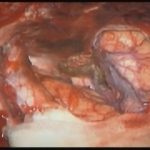

術中写真

摘出 中